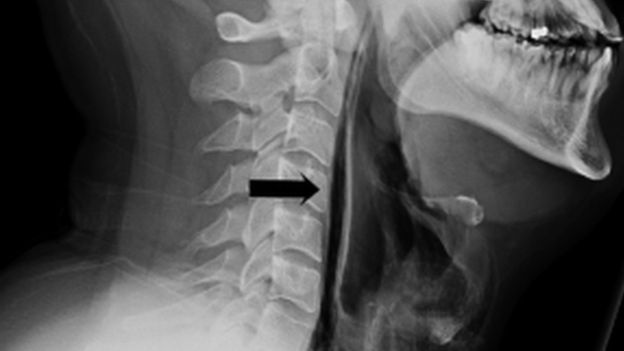

Sering tahan bersin, tenggorokan pria ini akhirnya pecah